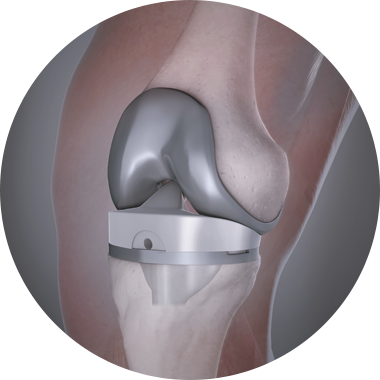

관절염의 수술적 치료로는 인공관절 수술이 가장 흔하지만, 인공관절 수술을 할 만큼

연골 손상이 심하지 않다면 내측으로 치우친 체중 부하를 정상적인 외측 관절로

이동시키는 ‘무릎관절 교정 절골술’을 시행합니다.